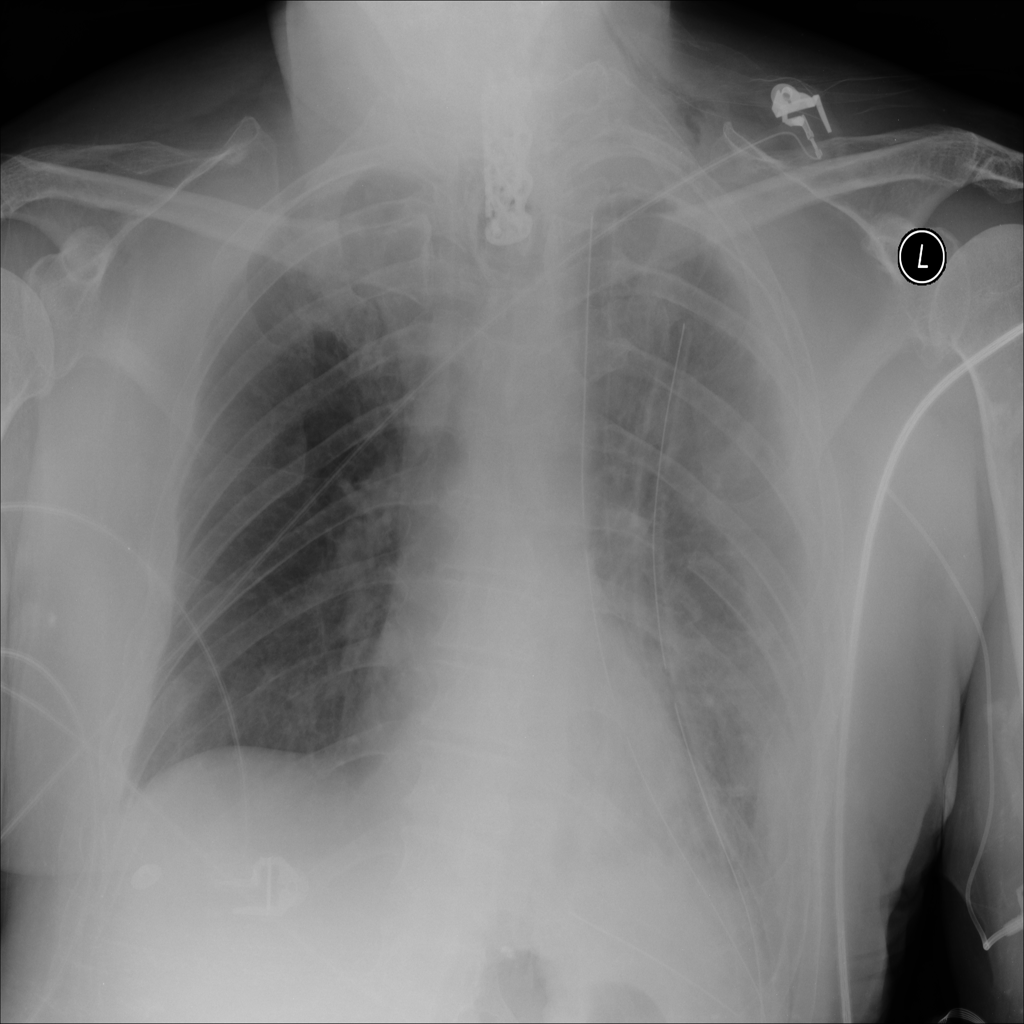

PAT-B0DB · IMG-003Emphysema

PAT-B0DB · IMG-003

PA